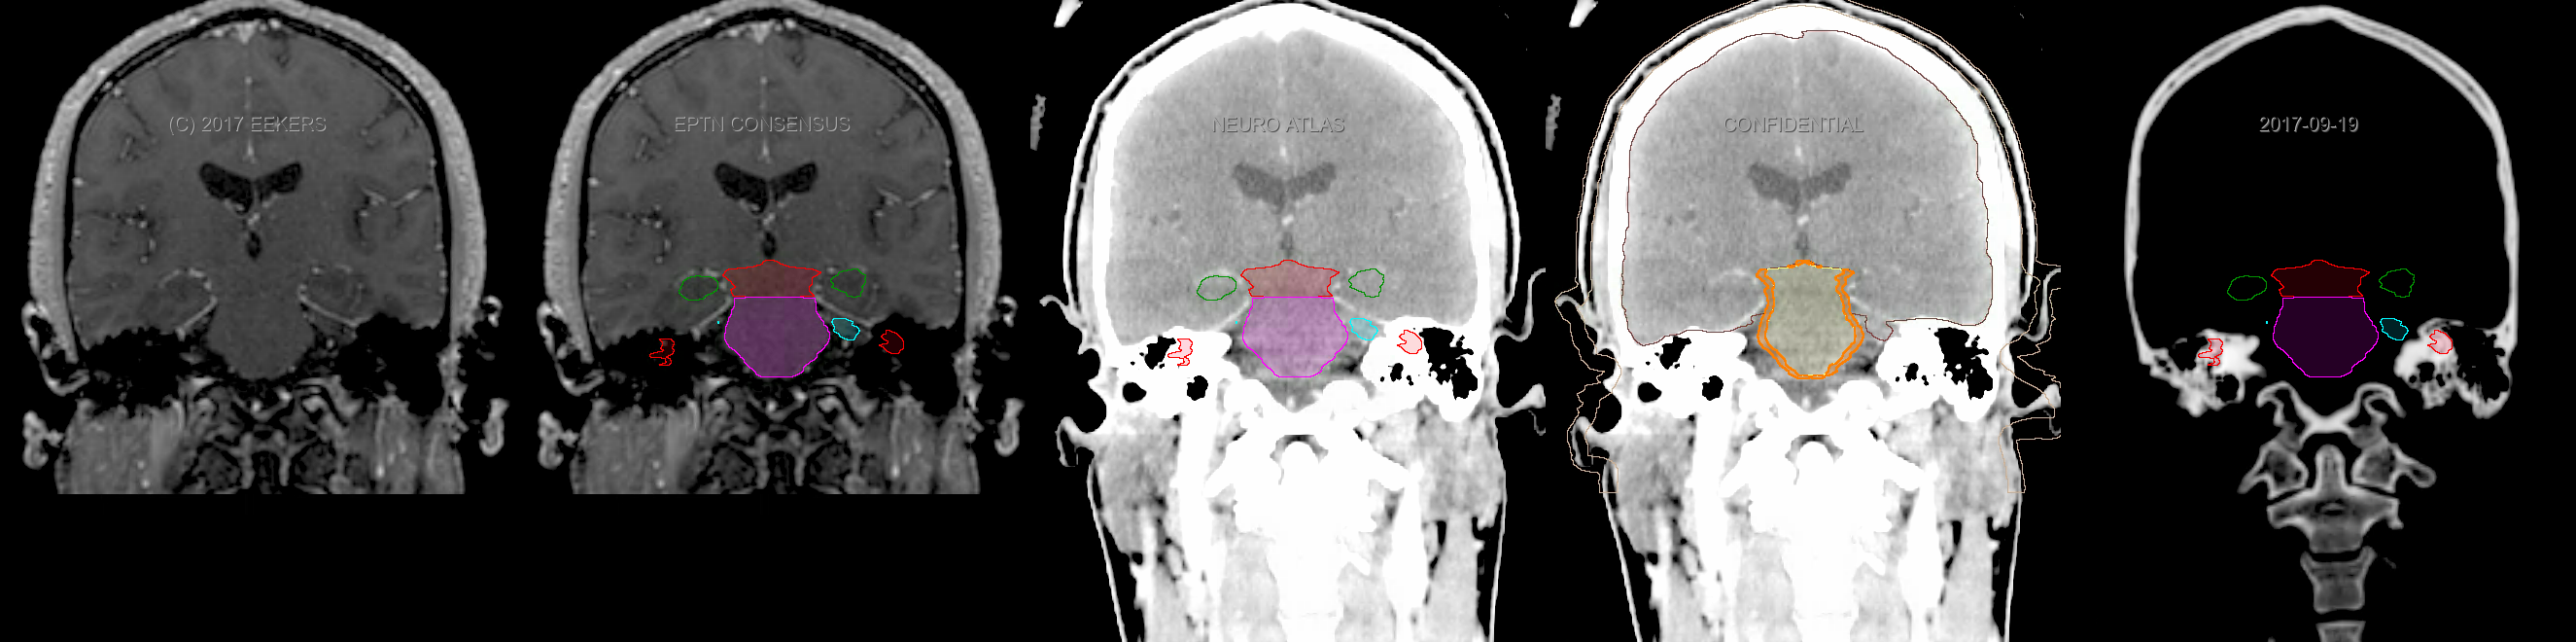

Three-dimensional delineation of the fifteen consensus OARs for neuro-oncology are shown on CT and 3 Tesla (3T) MR images (slice thickness 1 mm with intravenous contrast agent). All are presented in transversal, sagittal and coronal view.

From left to right: MR without structures, MR with structures, CT (WW/WL 120/40) with structures, CT (WW/WL 120/40) with Brain and Brainstem Surface, CT (WW/WL 1500/120)with structures